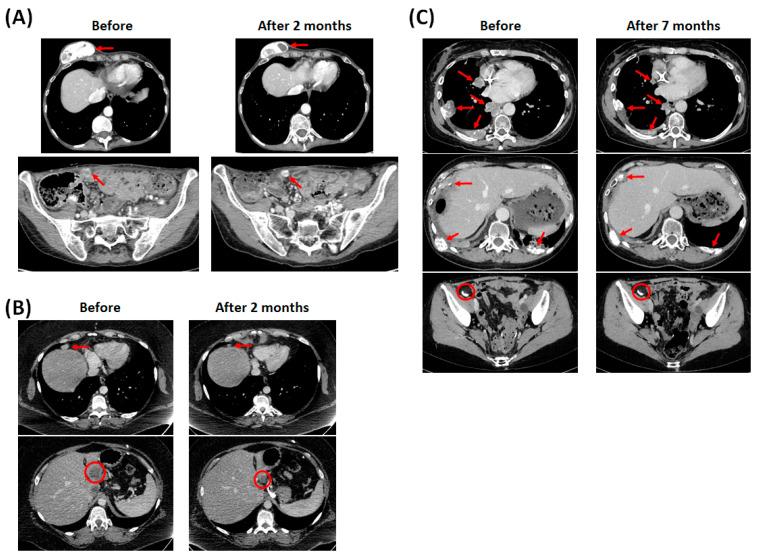

Low-grade serous carcinoma represents a minority of serous carcinoma. Although they have better prognosis than high-grade serous carcinoma, they respond poorly to chemotherapy. Thus, it appears necessary to find other treatments such as targeted therapies. Since or mutations occur frequently in low-grade serous carcinoma and lead to constitutively activated MAPK cascade, MEK inhibition should be effective in the treatment of low-grade serous carcinoma. So, we wanted to evaluate the clinical benefit of MEK inhibitors in the management of advanced-stage low-grade serous carcinoma harboring or mutation. We report a case series of three women with advanced-stage low-grade serous carcinoma harboring mutation who had stabilization of their disease during several months under targeted therapy combining anti-EGFR antibody and MEK inhibitor. We performed in vitro experiments, confirming the effectiveness of MEK inhibitor on the -mutated OVCAR-5 cell line, and the constitutively activation of MAPK cascade in -mutated carcinoma. However, it seems that the anti-EGFR antibody does not provide any additional benefit. After whole exome analysis is carried out on the patient with the shortest response, we observed the appearance of RB1 loss-of-function mutation that could be a mechanism of resistance to MEK inhibitors in - of -mutated cancers. The MEK inhibitor is effective in the advanced stages of low-grade serous carcinoma harboring mutation with acceptable tolerance. RB1 loss could be a mechanism of resistance to MEK inhibitors in -mutated low-grade serous carcinoma.

低级别浆液性癌占浆液性癌的少数。尽管它们的预后比高级别浆液性癌好,但对化疗反应不佳。因此,似乎有必要寻找其他治疗方法,如靶向治疗。由于 或 突变在低级别浆液性癌中频繁发生并导致丝裂原活化蛋白激酶(MAPK)级联持续激活,抑制MEK在低级别浆液性癌的治疗中应该是有效的。所以,我们想评估MEK抑制剂在治疗携带 或 突变的晚期低级别浆液性癌中的临床益处。我们报告了一个病例系列,三名患有携带 突变的晚期低级别浆液性癌的女性,在联合抗表皮生长因子受体(EGFR)抗体和MEK抑制剂的靶向治疗下,病情稳定了数月。我们进行了体外实验,证实了MEK抑制剂对 -突变的卵巢癌细胞系OVCAR-5有效,以及在 -突变的癌中MAPK级联的持续激活。然而,抗EGFR抗体似乎没有提供任何额外益处。在对反应最短的患者进行全外显子组分析后,我们观察到RB1功能丧失突变的出现,这可能是 -突变癌症对MEK抑制剂耐药的一种机制。MEK抑制剂对携带 突变的晚期低级别浆液性癌有效,耐受性可接受。RB1缺失可能是 -突变的低级别浆液性癌对MEK抑制剂耐药的一种机制。